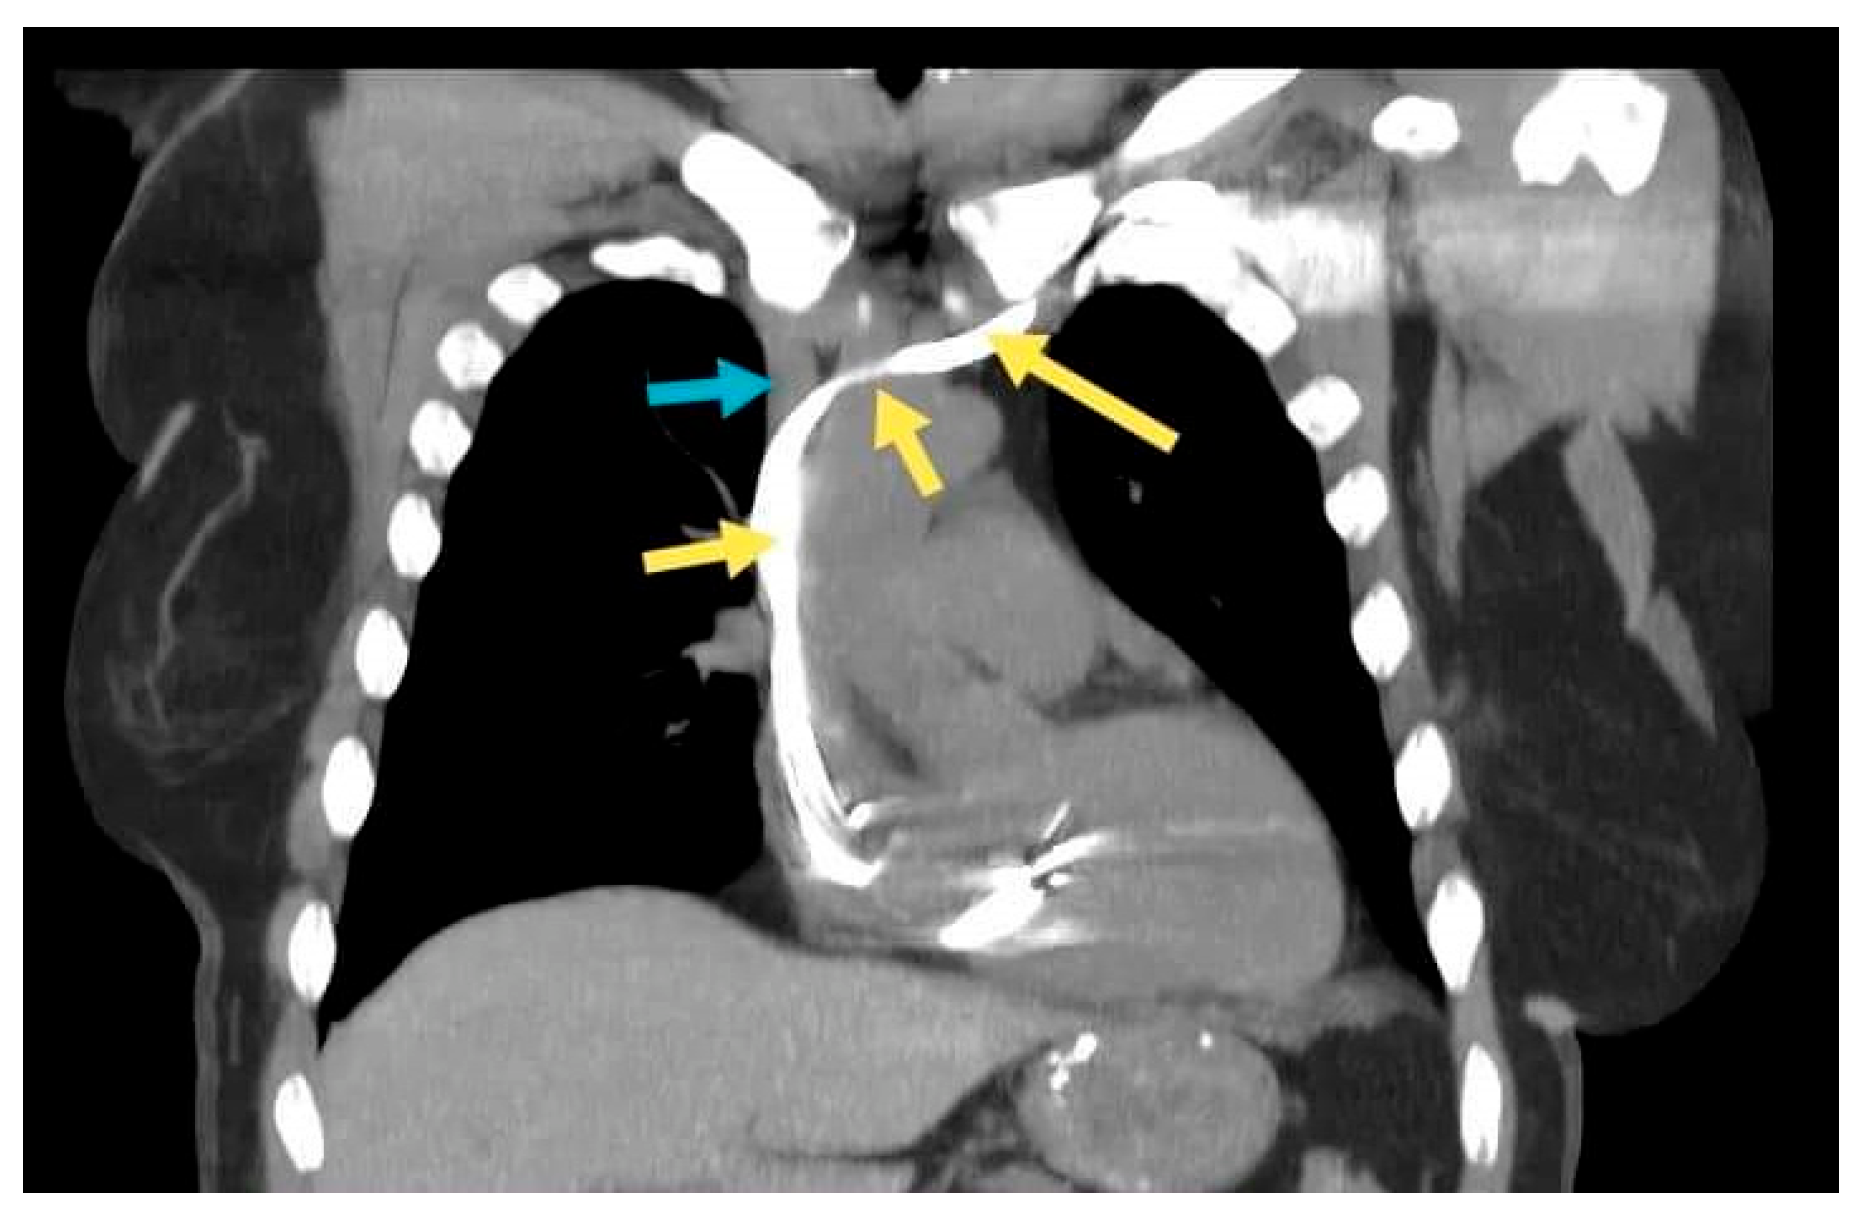

2.3. Case 3. (Type II)